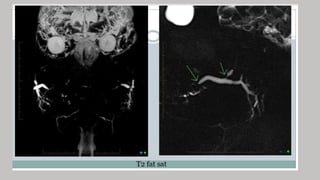

MR sialography

• MR is used to diagnosis of lesions of the salivary glands

• Now contrast studies are useful in differentiating benign or low

grade malignant from the high grade malignant tumors

• Contrast enhancement is useful in differential diagnosis of cystic

from solid lesions, and when determining the degree of perineural

spread of malignant disease

Sequences used in MR sialography

•T1- weighted and T2-weighted images are taken with a slice

thickness of 3mm and interslice gap of 1mm.

•FSE T2-weighted image may require fat suppression

• Gadolinium enhanced scans with T1 weighting and fat

suppression are obtained in axial plane.

•Sagittal and coronal images may be obtained as required